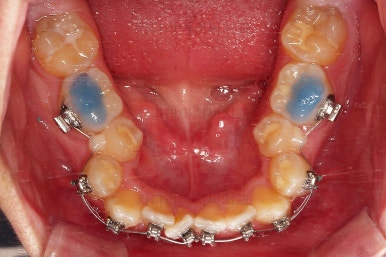

적절한 시기에 발치를 해주고요.

발치 공간을 이용해서 치열을 가지런하게 해줍니다.

가지런하게만 해도 발치공간이 거의다 없어져가요.

입이 많이 안들어가야 하는 케이스라 얼굴모습을 중간중간 확인을 많이 해주고요.

남은 공간을 자연ㅇ스럽게 더 닫아주고요.